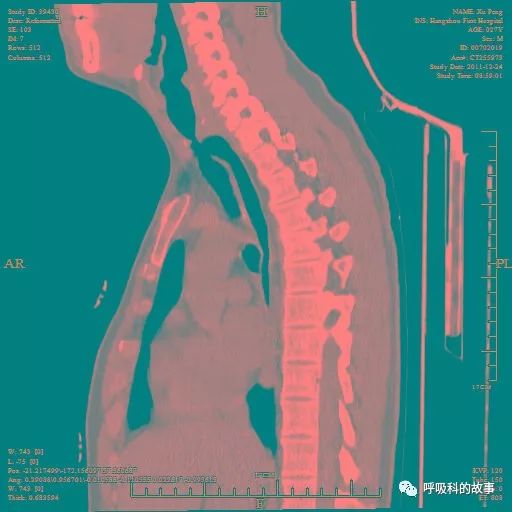

图5胸部CT气管三维重建示气管在第二胸椎水平与食管有一瘘道相连,瘘道上方气管狭窄。